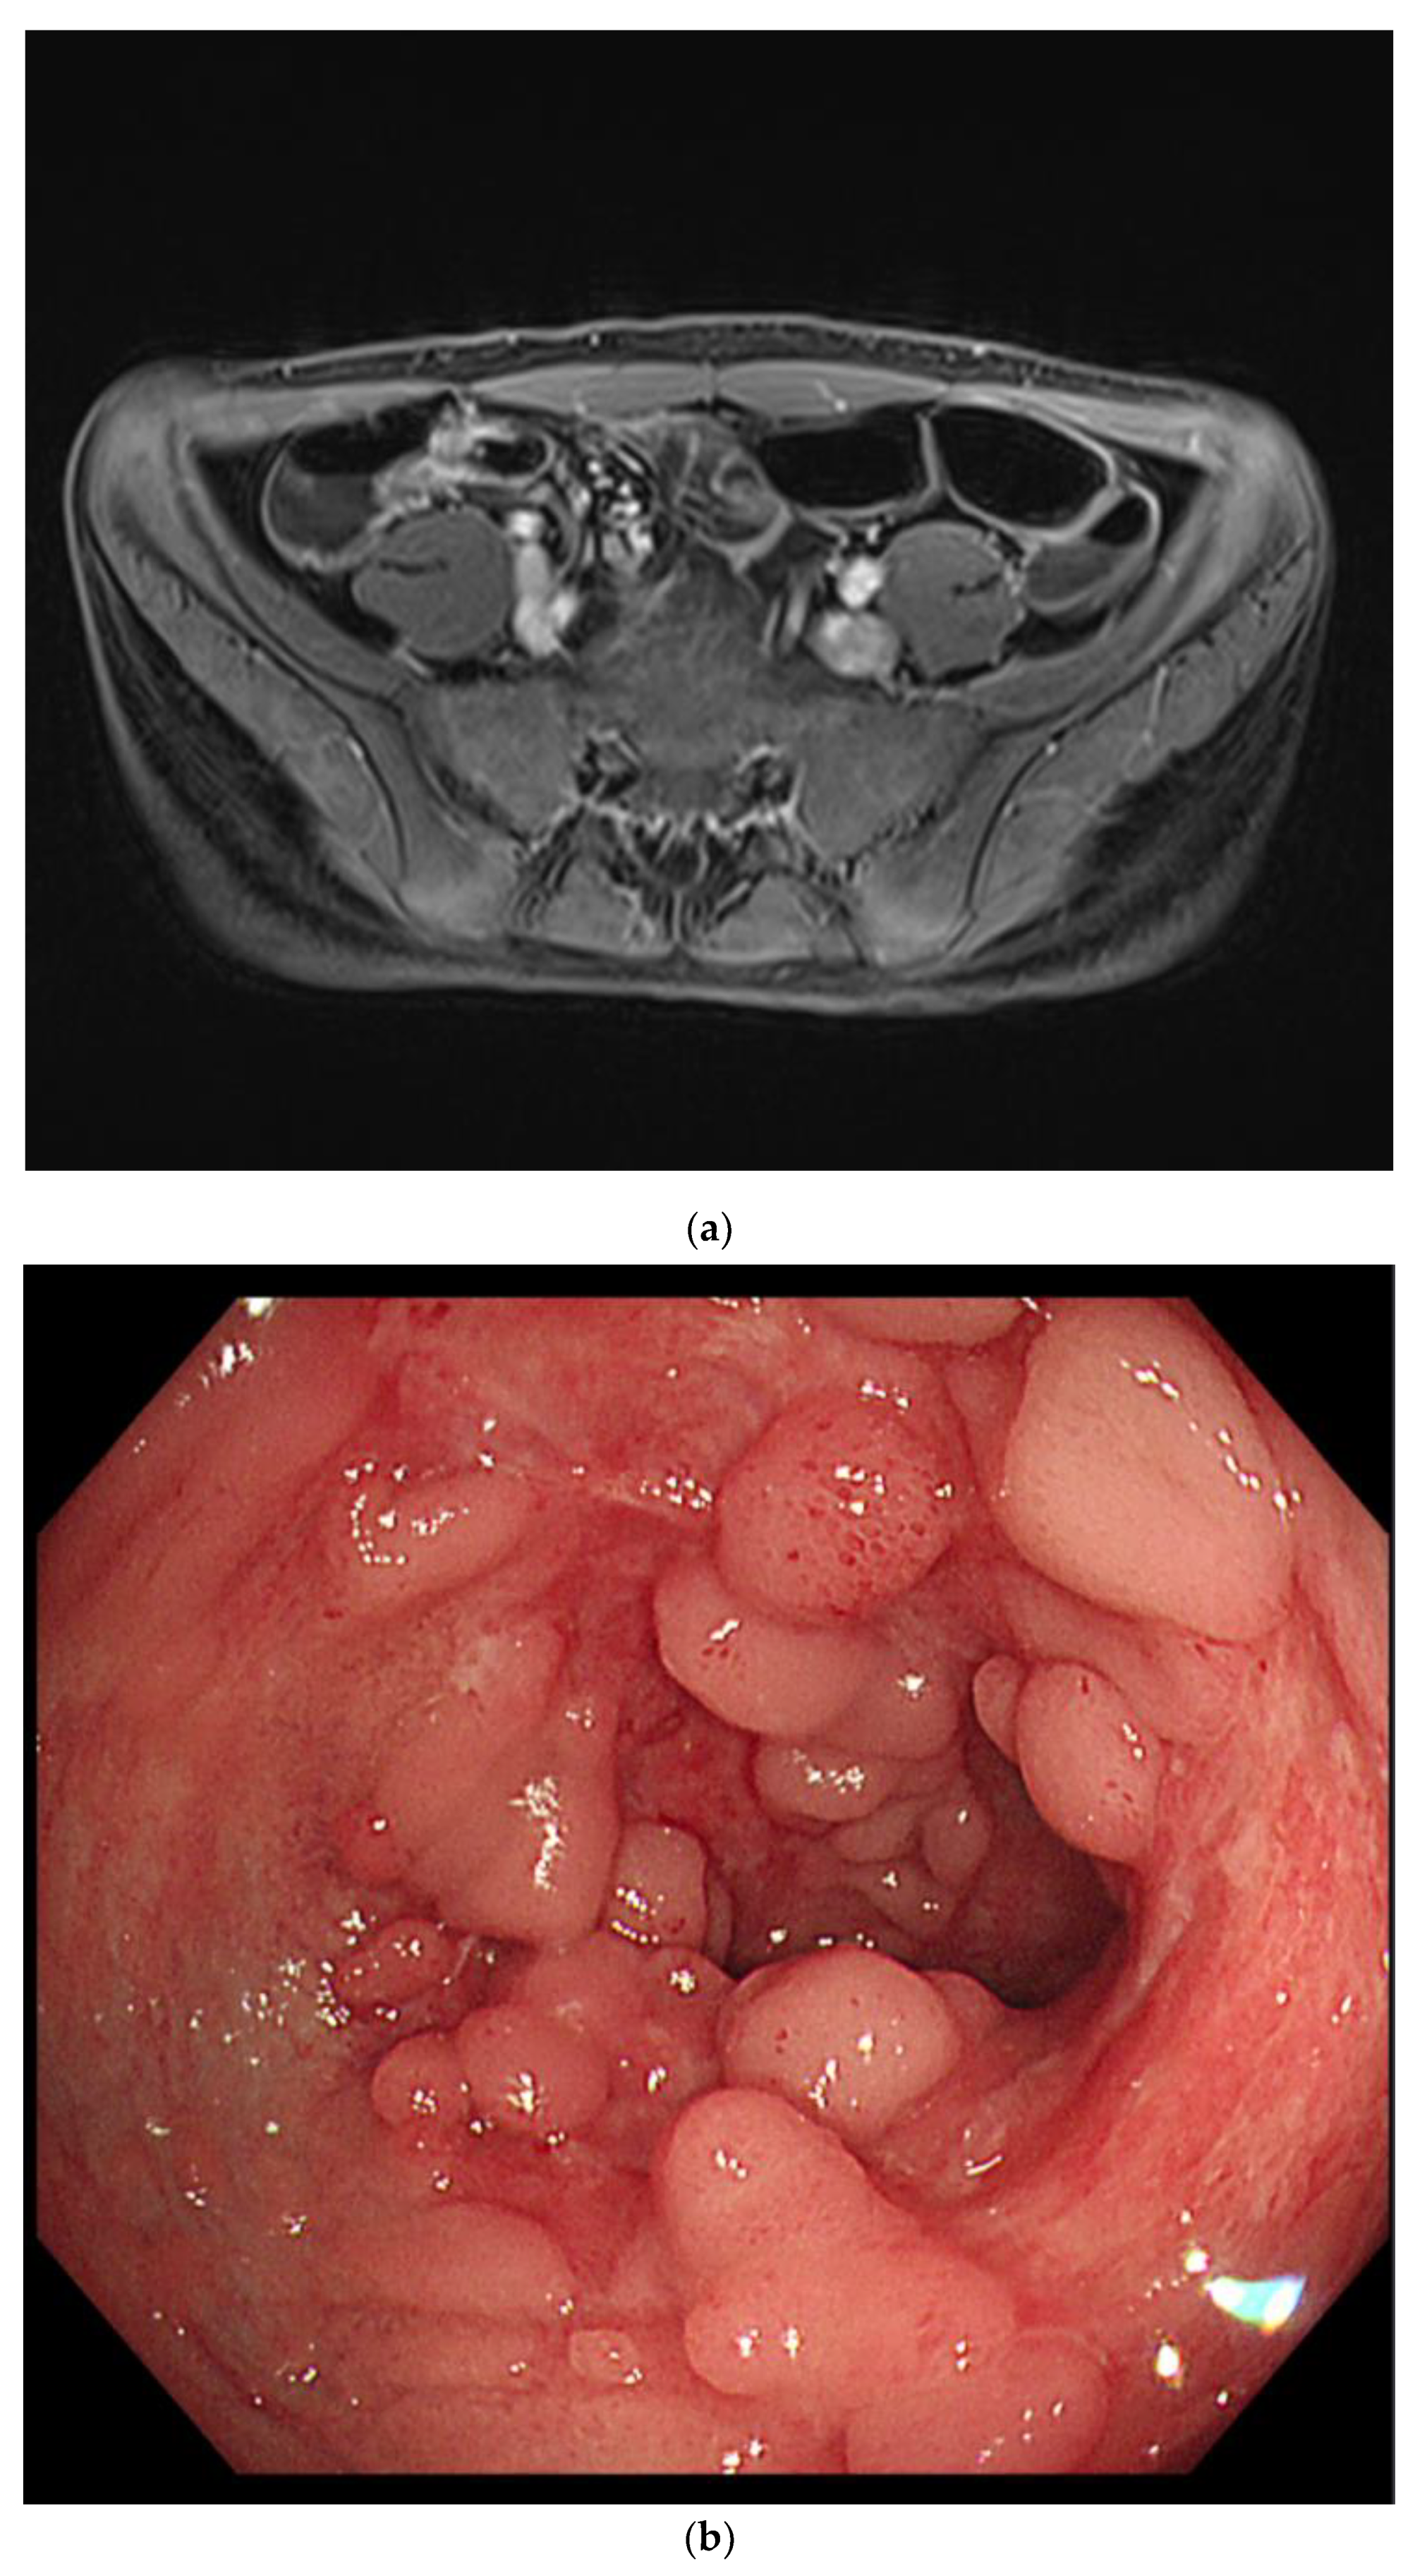

On the third day in the ICU, the patient had massive hematochezia (900 cc), which was the first episode of bloody stools. Vital signs were stable, and no sources of acute bleeding, such as extravasation or pseudoaneurysms, were observed on CT. On colonoscopy, ulcerations were observed in the distal terminal ileum and ileocecal valve. Although observation of the colonic mucosa was limited to blood, there was no focus of active bleeding (Figure 3).

Figure 3.

Initial endoscopic findings revealed ulcerations around the ileocecal valve.

Intermittent episodes of bloody stools continued, and symptoms and vital signs were controlled through supportive care, including intravenous hydration and blood transfusion. CD was suspected, so he was treated with exclusive enteral nutrition with a steroid to control the myocarditis. On the 13th day of admission, the patient had no symptoms other than intermittent bloody stools. All cardiac markers were normal, and sST2 was also reduced to 98 ng/mL. Therefore, the patient was transferred to the general ward for diagnosis and treatment of IBD. MR enterography revealed terminal ileitis without stricture. Gastroduodenocolonoscopy revealed improvement in the ileocecal valve and terminal ileal ulceration with no other lesions (Figure 4).

Figure 4.

Magnetic resonance enterography demonstrated wall thickening of the distal ileum, including the ileocecal valve (a). Colonoscopy revealed healing scars and pseudopolyps of the terminal ileum (b).